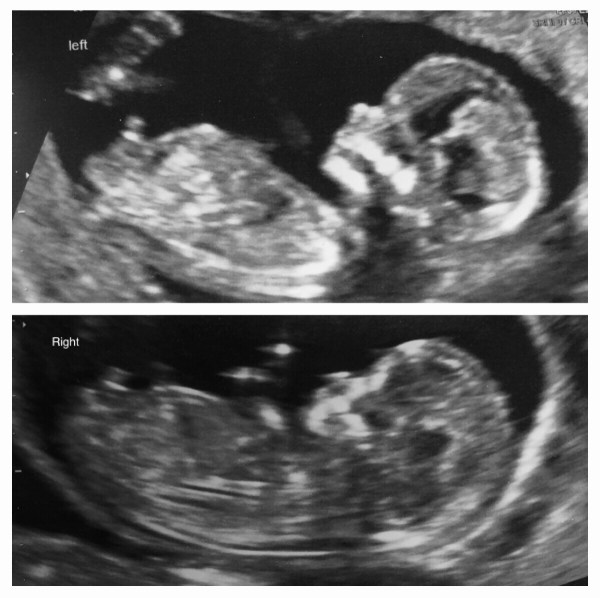

It has now been a few days since my scan and I am an impatient person, so I started to wonder about the nub theory I’ve seen mentioned. I’ve never tried it with either of my other babies, but I thought it would be a bit of fun.

Research showed that the nub of the babys genitals seems to either lay paralell to the spine in the case of a girl, or stick up at atleast 30 degrees for a boy. The nub is clearly visible on both my babies scans, and clearly sticking up. 2 boys? I looked back at my previous 2 12 week scans, but neither actually showed the nub so I cannot confirm or discount it! Websites say that if the nub is clear it has 88% sucess rate… however there are lots of stories where it has been wrong and poo-pooed by medical professionals.

I am taking this with a pinch of salt, however, it is good to have a bit of prewarning, since I was really hoping to have atleast one girl in my brood that I actually get to raise, so atleast when I have it confirmed (or denied) I won’t be too shocked.